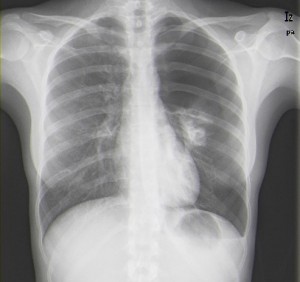

La radiografía es la primera opción por su rapidez, facilidad y coste. Se elige las posiciones anteroposterior y lateral para obtener información más completa y poder localizar la lesión en todos los ejes.